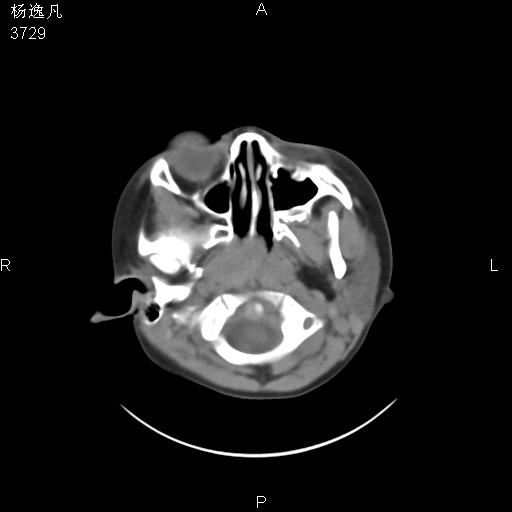

男性,5岁,面部受外伤,余无特殊

骨窗

鼻咽顶后变窄。顶后壁增厚,考虑腺样体肥大。其它未异常/

1、右面部及颞部软组织肿胀。

2、腺样体肥大。

头颅ct平扫未见明确外伤性征象,右侧面部及颞部软组织肿胀,后鼻腔软组织影增大,增厚,鼻咽顶部变窄,考虑鼻咽腺样体增值肥厚。